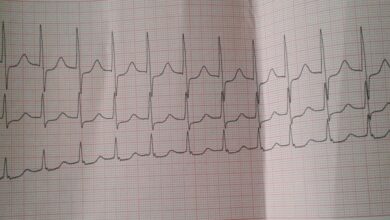

Основные симптомы эндокардита включают лихорадку, слабость, одышку, боли в суставах и изменения на коже. Диагностика данного заболевания требует комплексного подхода.

Для точного выявления эндокардита могут быть проведены следующие процедуры: эхокардиография, анализы крови на наличие инфекции, биопсия клапанов сердца.